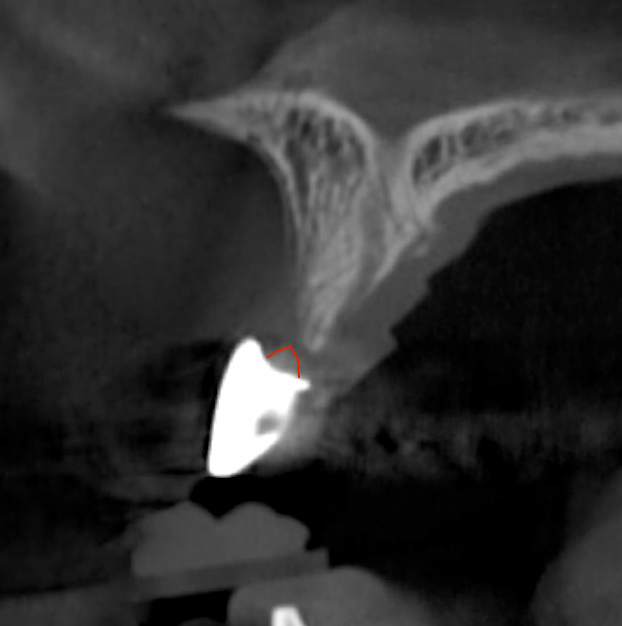

Tomographic images revealed a large tridimensional defect, with vertical and horizontal loss of bone extending to the apical third of teeth Nos. 6 and 8. Additionally, a buccal bone dehiscence was evident on tooth No. 5, and thin labial plates secondary to the orthodontic movement were present in several areas (Figure 3 and Figure 4).

After 3 months of post-orthodontic stabilization, a cone-beam computed tomography scan was taken to re-evaluate the results and plan the future treatment sequence. Tomographic images clearly showed vertical gains in alveolar height, including in the edentulous area corresponding to tooth No. 7 (Figure 10 through Figure 12). The apex of tooth No. 8 was forced-erupted beyond its socket and could be visibly located within the soft tissue.30,33